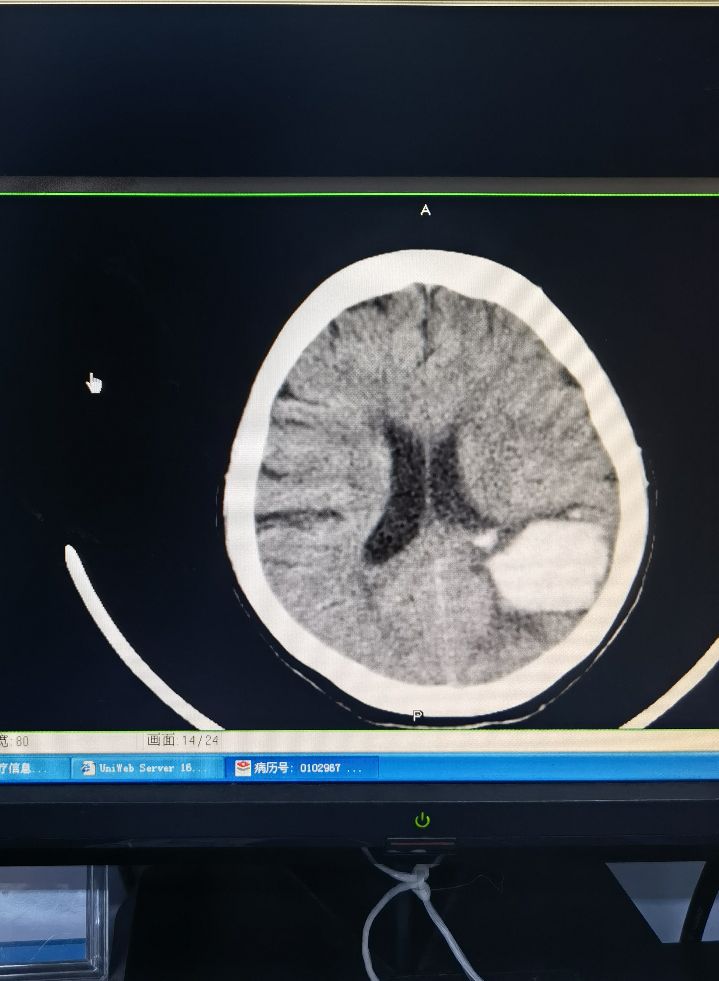

硬脑膜外血肿引流,高压氧治疗颅内出血

黑河市第一人民医院神经外科为黑河人民健康保驾护航